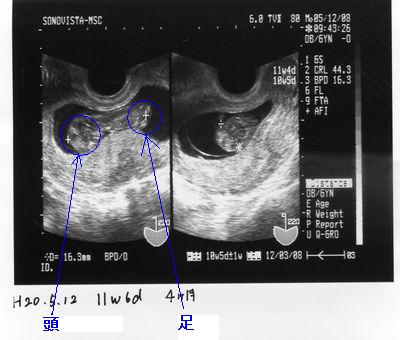

エコー写真ですが、左の写真で黒くヒョウタンの形になってるのが胎盤でその中にある白く細長い物体がJ’rらしく、身長は約4Cmで左側が頭で右側が胴体、足となってるそうです。

足や腕はまだ数ミリ程度でしかなく出来かけといった感じです。

この状態で約4ヶ月。

今のところ順調に成長しているらしく、予定日は今年の11月後半とのこと。